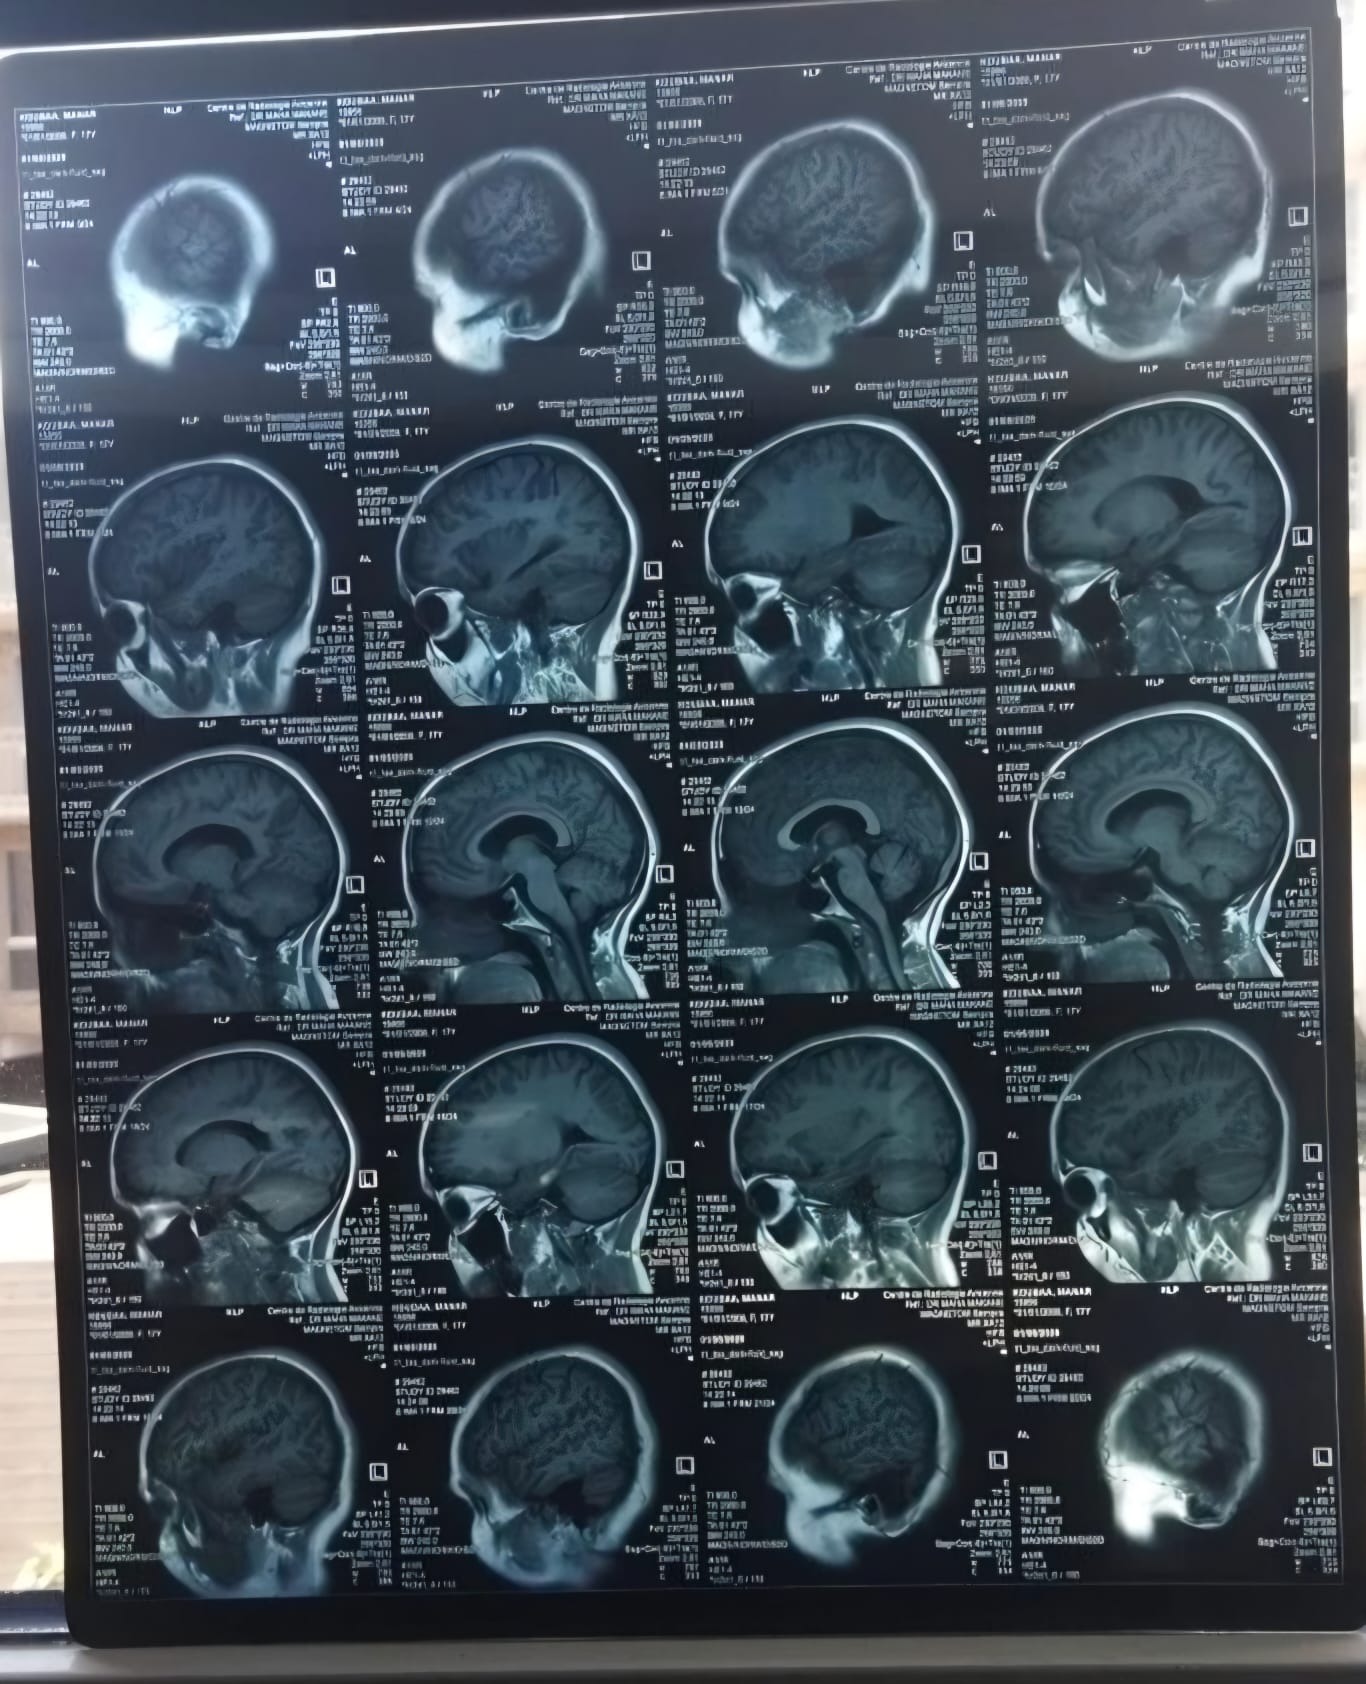

Ik ben Manar, ik ben 17 jaar oud. In mei 2025 heb ik de diagnose MS gekregen. Ik had veel last van duizeligheid, vermoeidheid en uiteindelijk dubbelzien. Uit verschillende onderzoeken is de diagnose MS vastgesteld. Iedere maand krijg ik via een infuus in het ziekenhuis medicatie toegediend, dit zorgt ervoor dat de ziekte geremd wordt. Helaas merk ik toch nog veel lichamelijke klachten waar ik dagelijks mee te maken heb. Dit beinvloed mijn dagelijks leven en het voortzetten van mijn studie. Al hamdoulilah 3la kouli hal.

Om te voorkomen dat mijn lichamelijke gezondheid niet verder achteruit gaat wil ik een stamcelbehandeling ondergaan in het buitenland. Een HSCT-behandeling, een intensieve behandeling waarbij het immuunsysteem wordt gereset. Deze behandeling kan de ziekte niet genezen, maar wel stopzetten en verdere verergering voorkomen. Deze behandeling kost € 65.000. Ik vertrouw er op met behulp van Allah en onze geweldige ummah dit bedrag te kunnen verzamelen, in sha allah.